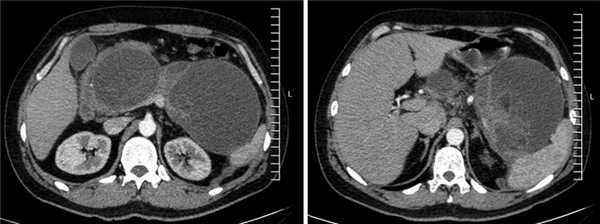

Рис. 2. Псевдокисты поджелудочной железы с секвестрами (компьютерная томограмма органов брюшной полости с внутривенным контрастированием).

Для определения возможности эндоскопического дренирования гигантской псевдокисты пациенту была выполнена эндоскопическая ультрасонография, по данным которой в проекции головки-хвоста ПЖ определись два крупных жидкостных коллектора с ровными четкими контурами размерами 170×130 и 120×180 мм. Оба жидкостных скопления имели четкие границы, были правильной овальной и округлой формы с гиперэхогенной капсулой толщиной до 3 мм и содержали значительное количество гиперэхогенного содержимого с неровными контурами — секвестры. ПЖ просматривалась фрагментарно, контуры ее четкие и неровные, структура диффузно неоднородная, сниженной эхогенности, панкреатический проток в доступных участках не визуализировался (рис. 3).

По данным контрольной КТ органов брюшной полости через 4 нед, в области головки ПЖ полость кисты отсутствует, в области хвоста псевдокиста ПЖ значительно «спалась» до внутреннего края нитинолового стента (рис. 6).

Рис. 6. Компьютерная томограмма органов брюшной полости с внутривенным усилением (после лечения).